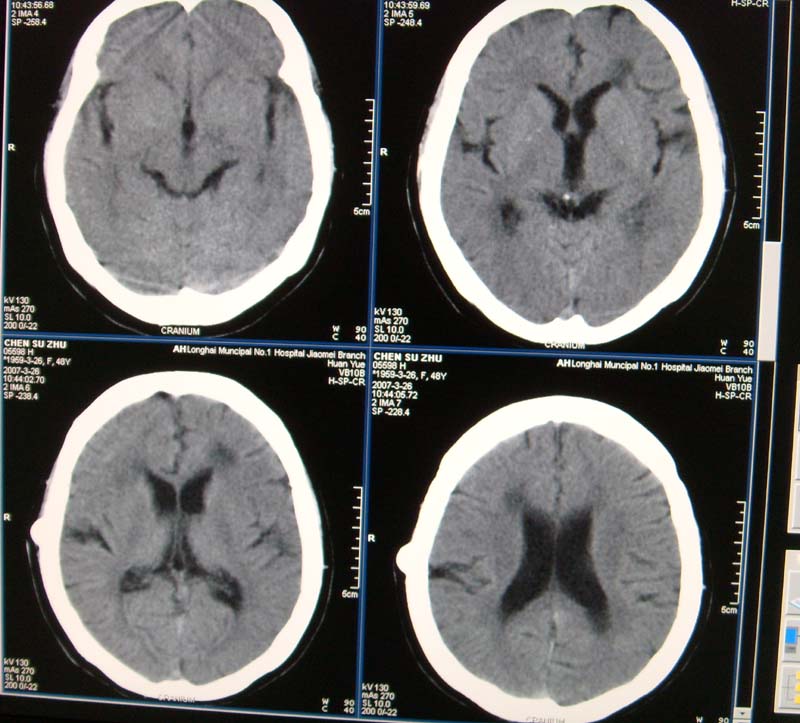

标题: CT8208:女,48岁,反复头晕半年余,无听力、视力障碍 [打印本页]

标题: CT8208:女,48岁,反复头晕半年余,无听力、视力障碍

患者,女,48岁,反复头晕半年余,无听力、视力障碍。病人已手术,结果明天传。

内听道没有加层薄扫,显示不太清,所以鉴别听神经瘤和脑膜瘤困难.左额叶低密度是梗塞?

左侧桥小脑角区高密度肿块,周围无水肿及明显占位效应,岩骨尖受压吸收,内听道未见扩大,无听力异常,右侧颅骨外板高密度影,边缘锐利,考虑:左侧脑膜瘤,右侧颅骨骨瘤。左侧岩骨尖有破坏,三叉神经瘤待排。